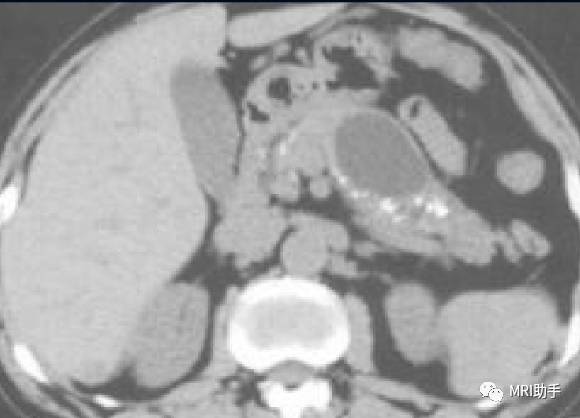

胰头癌常可见胰头增大,胰体尾部萎缩。胰头钩突部癌表现为胰头钩突由三角形变成球形,将肠系膜上动静脉向内上方推移。胰体尾部癌往往体积较大,其内可见坏死区。

胰体尾部癌:强化程度低于正常胰腺实质